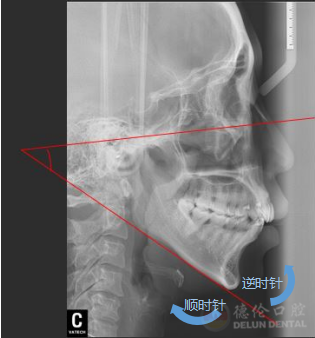

颌平面的逆时针旋转,即是下巴往前翘

“按照常规方案,这种情况是不太适合推磨牙远移,因为推磨牙远移会造成整个颌平面的顺时针旋转,就会出现面型更不好看。但是因为给她设计了压低、另外打了支抗钉来控制它的矢状向和垂直向,就没有出现顺时针旋转,反而出现了整个颌平面的逆时针旋转,下巴还变好看了。”熊小琴主任在接受访问时解释道,此案例的难点在于垂直向控制,在没有给患者进行手术的情况下解决了患者主诉、满足了个性化要求,矫牙结束后患者自己感觉很满意。